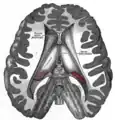

Additional images

The pineal body is labeled in these images.

Dissection showing the ventricles of the brain